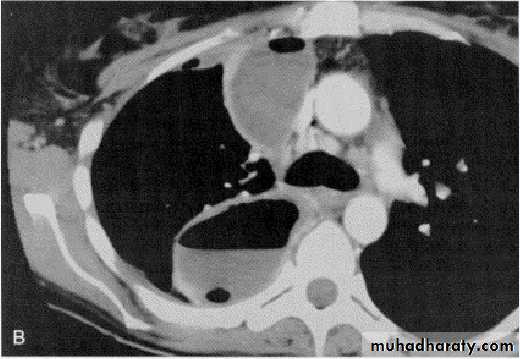

Computed tomography scan of the chest demonstrates a mass in the right upper lobe adjacent the pleura (*). Irregular soft-tissue thickening of the pleural surface (arrow) and pleural effusion (E) are present. The findings are most consistent with primary lung neoplasm with pleural metastasis and malignant pleural effusion. Results of thoracentesis were positive for malignant cells (adenocarcinoma).